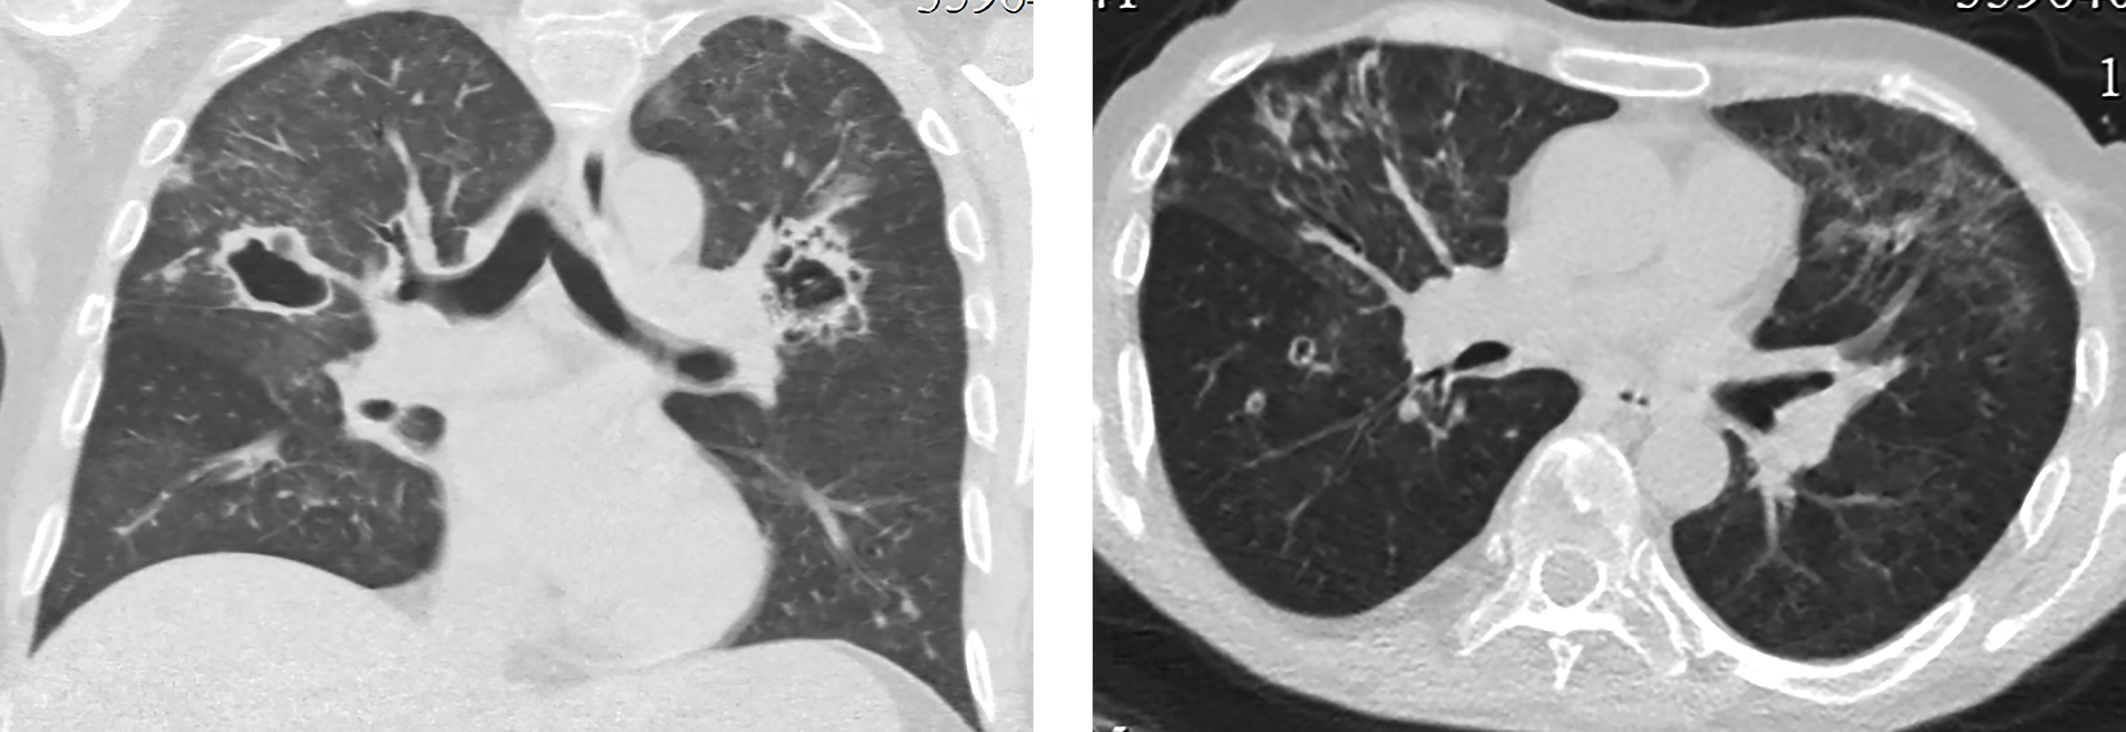

У пациента были взяты посевы, выполнена микроскопия и ПЦР на туберкулез. Все показатели оказались отрицательными. Туберкулез был исключен. По данным микроскопии с окрашиванием калькофлуором белым, теста на галактоманнан, посева на грибы диагностирован инвазивный аспергиллез с поражением обоих легких. Инициирована антимикотическая (вориконазол) и антибактериальная (ванкомицин, левофлоксацин) терапия, продолжена противовирусная терапия, гидрокортизон, отхаркивающая терапия, гепатопротекторная и противоязвенная терапия. На фоне проводимого лечения отмечалась значительная положительная динамика, как клинически, так и при КТ-контроле — через 9 дней отмечен регресс воспалительных изменений в обоих легких (рис. 8).

Рисунок 8. КТ грудной клетки через 9 дней после начала антимикотического лечения: регресс воспалительных изменений в легких.